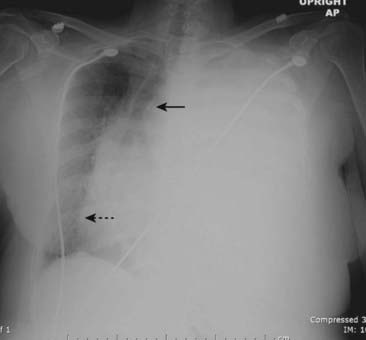

Figure 6-1 Dressler syndrome (postpericardiotomy/postmyocardial infarction syndrome).

A left pleural effusion (A) is present (solid black arrows). This syndrome typically occurs 2 to 3 weeks after a transmural myocardial infarct. It also can occur following pericardiotomy such as occurs in patients undergoing coronary artery bypass surgery, as in this case. The combination of chest pain and fever, left pleural effusion, patchy left lower lobe airspace disease, and pericardial effusion several weeks following a myocardial infarction or open-heart surgery should suggest the syndrome. It usually responds to high-dose aspirin or steroids. This patient has a dual lead pacemaker in place and, on the lateral projection (B), the leads are seen in the region of the right atrium (dotted black arrow) and right ventricle (arrowhead).